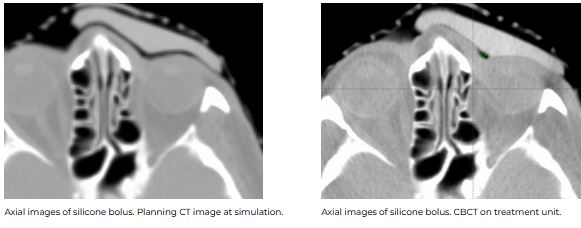

CT images were acquired with and without an internal eye shielding (IES) for the 3D printed rigid and flexible silicone bolus. The rigid bolus included a soft bolus plug over the eye to allow placement of the IES.

Both showed good conformity to the body surface. The air gap volume over the inner canthus was 1.27 cc for the 3D rigid bolus, corresponding to the location of the soft bolus plug. The measured air gap volume under the silicone bolus in this same region was 0.24 cc.

The flexible and malleable nature of the silicone bolus required careful placement for daily treatment to ensure the proper fit. A CBCT was taken daily to verify the bolus position.